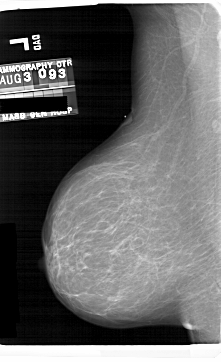

A_1690_1.RIGHT_MLO

LEFT_MLO LINES 6871 PIXELS_PER_LINE 4186 BITS_PER_PIXEL 12 RESOLUTION 43.5 NON_OVERLAY